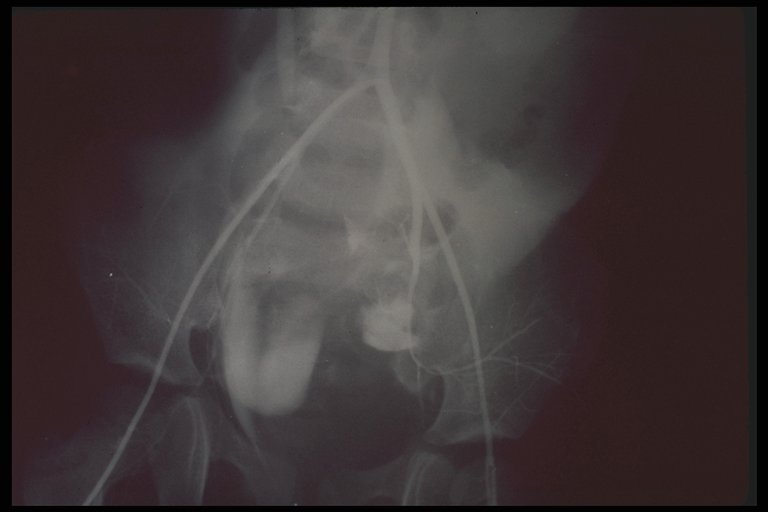

Angiogram in the child with pelvic fracture demonstrates the large retroperitoneal hematoma on the left side displaced the bladder upward

Selective angiogram demonstrated the tear of internal iliac vessels(artery)